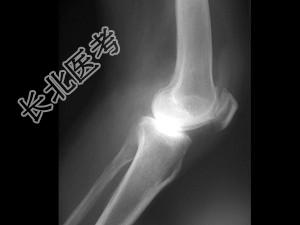

- 单项选择题女,50岁, 手指关节肿痛,晨僵, 结合图像,最可能诊断是 ( )

A、关节结核

B、牛皮癣性关节炎

C、痛风性关节炎

D、类风湿关节炎

E、Reiter综合征